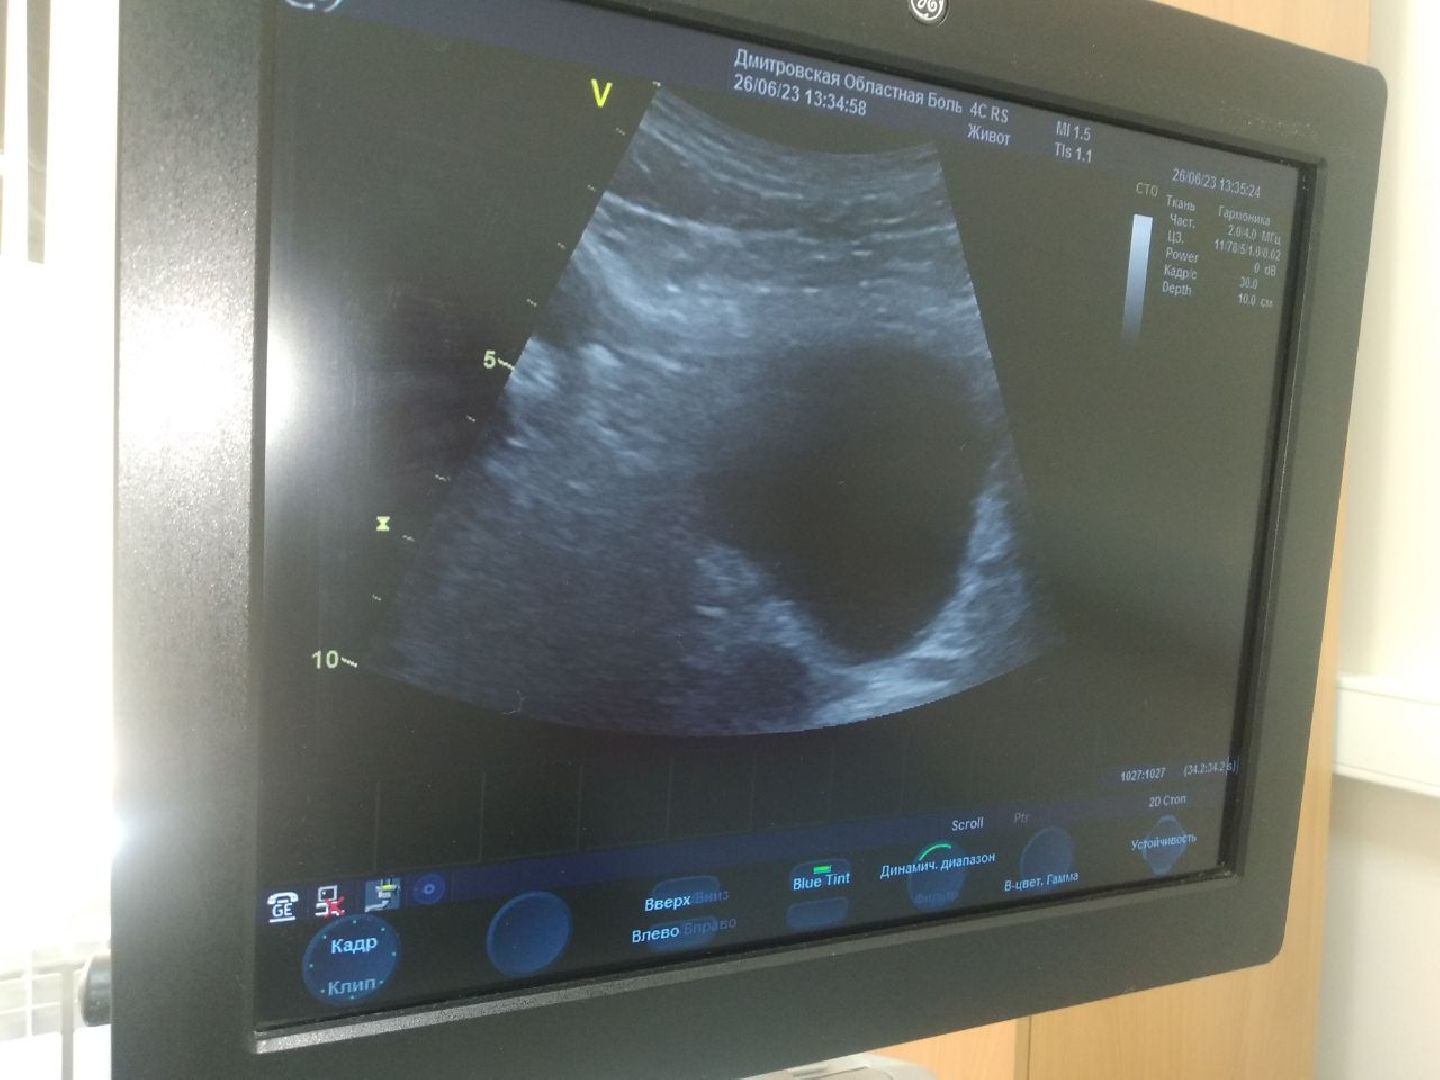

«Оборудование для ультразвуковой диагностики здесь очень хорошее, достаточно современное, удобное. Сложности пока возникают при работе с пациентами, все-таки новая для меня специализация. Но я в своих силах уверена», — добавила Симонова.